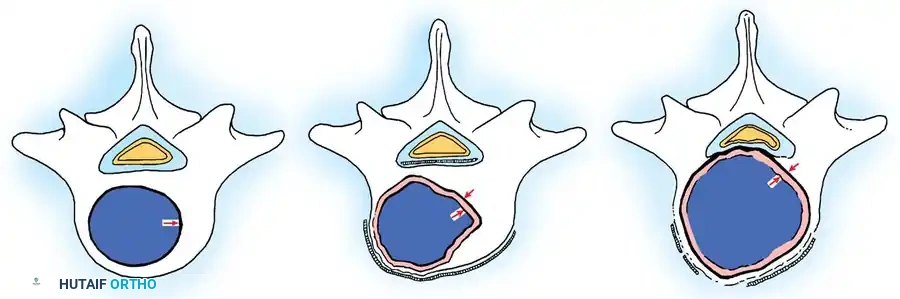

Fig. 41-30: Enneking staging of benign spinal tumors. Capsule of tumor is indicated by 1, and reactive pseudocapsule is indicated by 2. Stage 3 aggressive benign tumors can expand through the posterior vertebral wall and compress the cord. The pseudocapsule is vascularized reactive tissue and can adhere to the dura.

Stage 1: Latent Tumors

These lesions (e.g., asymptomatic osteochondromas, small eosinophilic granulomas) are inactive, well-marginated, and do not progress. They typically require no treatment other than observation. If surgery is mandated for diagnosis or mechanical symptoms, an intralesional excision (curettage) is sufficient.

Stage 2: Active Tumors

Stage 2 tumors (e.g., osteoid osteoma, standard osteoblastoma, aneurysmal bone cysts) grow slowly and cause symptoms, usually pain or deformity. They possess a reactive pseudocapsule. Treatment usually involves en bloc excision where anatomically feasible, though meticulous intralesional excision combined with local adjuvants (liquid nitrogen, phenol, or polymethylmethacrylate [PMMA]) often suffices.

Cross-sectional representation demonstrating the expansion of an active Stage 2 benign lesion within the vertebral body, respecting the outer cortical margins but requiring meticulous intralesional clearance.

Stage 3: Aggressive Tumors

Despite being histologically benign, Stage 3 lesions (e.g., giant cell tumors, aggressive osteoblastomas) are locally destructive. They breach the tumor capsule, invade local compartments, and have a high propensity for recurrence.

Cross-sectional view of a Stage 3 aggressive benign tumor breaching the posterior vertebral wall, highlighting the necessity for wide excision to prevent local recurrence.

Wide excision—removal of the tumor with a continuous cuff of normal, healthy tissue—is the oncologic treatment of choice. A marginal excision (dissecting through the reactive pseudocapsule) leaves microscopic disease and results in unacceptably high recurrence rates.